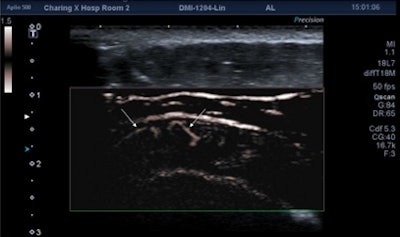

An Aplio 500 ultrasound scanner (Toshiba) with an 18-MHz probe was used to obtain ultrasound video clips and images. One of three radiologists with more than 10 years of musculoskeletal ultrasound experience independently read the studies and determined if vascularity was seen in the joints or tendons with power Doppler, SMI, or both methods.

While flow was demonstrated on both power Doppler and SMI in 58 cases, SMI alone showed vascularity in 40 cases. No cases of vascularity were shown on power Doppler but not on SMI. In 18 cases, no flow was detected by either technique. This difference in performance between power Doppler and SMI was statistically significant (Fisher's exact test: p < 0.001).

In more than half the cases where flow was identified using both techniques, SMI was judged to be either moderately or markedly better than power Doppler. This difference was also statistically significant (p = 0.02).